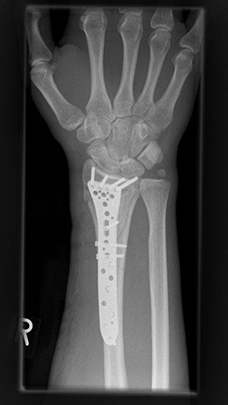

Komplexe rechtsseitige Unterarm-Handgelenksfraktur eines rechtshändigen jungen Mannes. Nach CT-Untersuchung offene Reposition und Rekonstruktion der komplexen Fraktursituation mit angepasster Plattenlänge. Sehr gute Funktion im weiteren Verlauf nach achsengerechter Ausheilung.

Komplexe rechtsseitige Unterarm-Handgelenksfraktur nach Osteosynthese

Komplexe rechtsseitige Unterarm-Handgelenksfraktur nach Osteosynthese, frontal